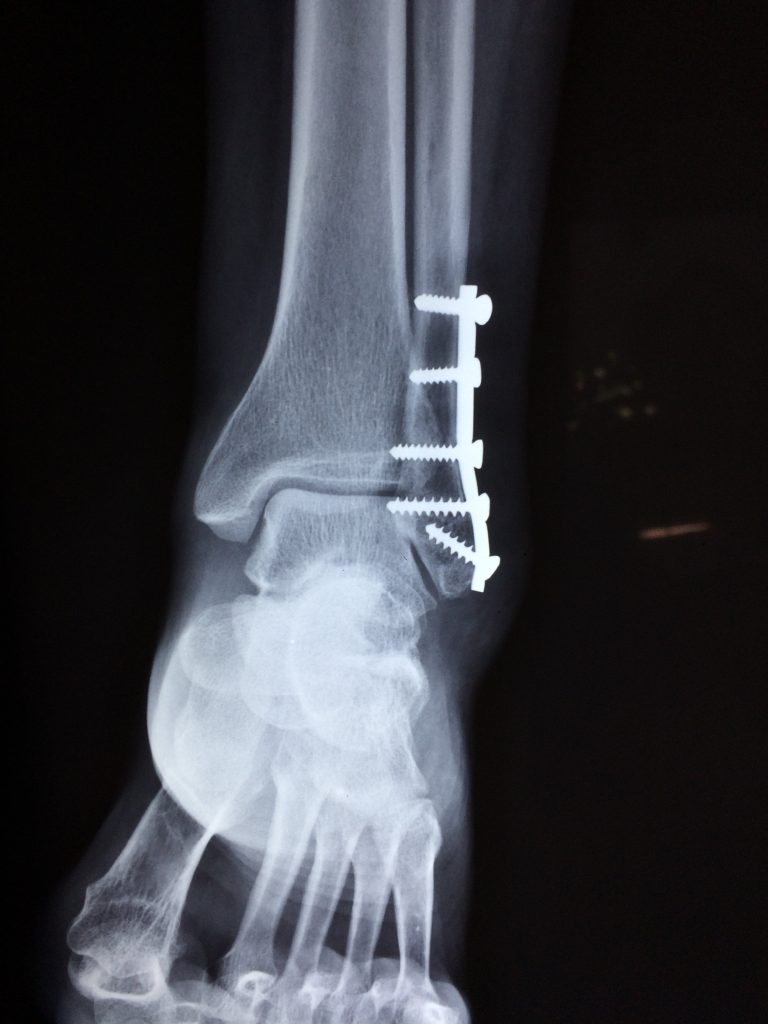

Die Physiotherapie nach Operationen des Bewegungsapparats fokussiert sich zunächst auf die Schmerzlinderung, die Reduktion von Schwellungen sowie Wiederherstellung der Funktionalität und der richtigen Belastung der betroffenen Eingriffsstelle. Zu diesen Operationen können künstliche Gelenke, Verplattungen, Verschraubungen, Beinachsenkorrekturen oder anderen orthopädischen Operationen zählen.